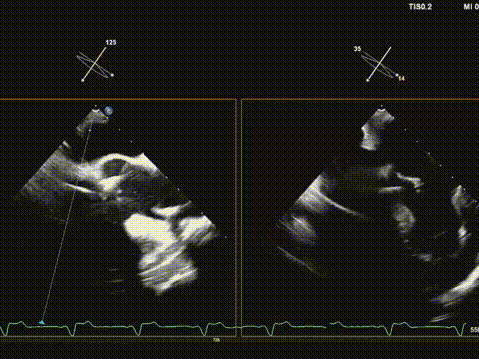

快速起搏下再次释放瓣膜至工作位,超声评估开口形态可,位置深度满意;

遂150快速起搏下完全释放瓣膜;

观察无瓣膜移动,回撤导丝后撤出系统;

术后超声评估,瓣膜位置深度满意,形态可,微量瓣周漏,最大血流速度1.53m/s,平均跨瓣压差4mmHg。